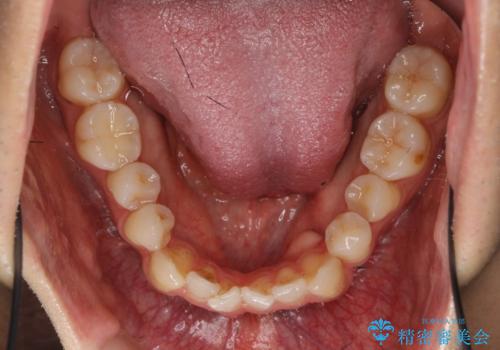

左上2が矮小歯で小さく、また、左の奥歯が反対咬合になっていました。

今回は下の前歯を1本抜くことで、下の奥歯をしっかり内側に傾けて治療を行いました。